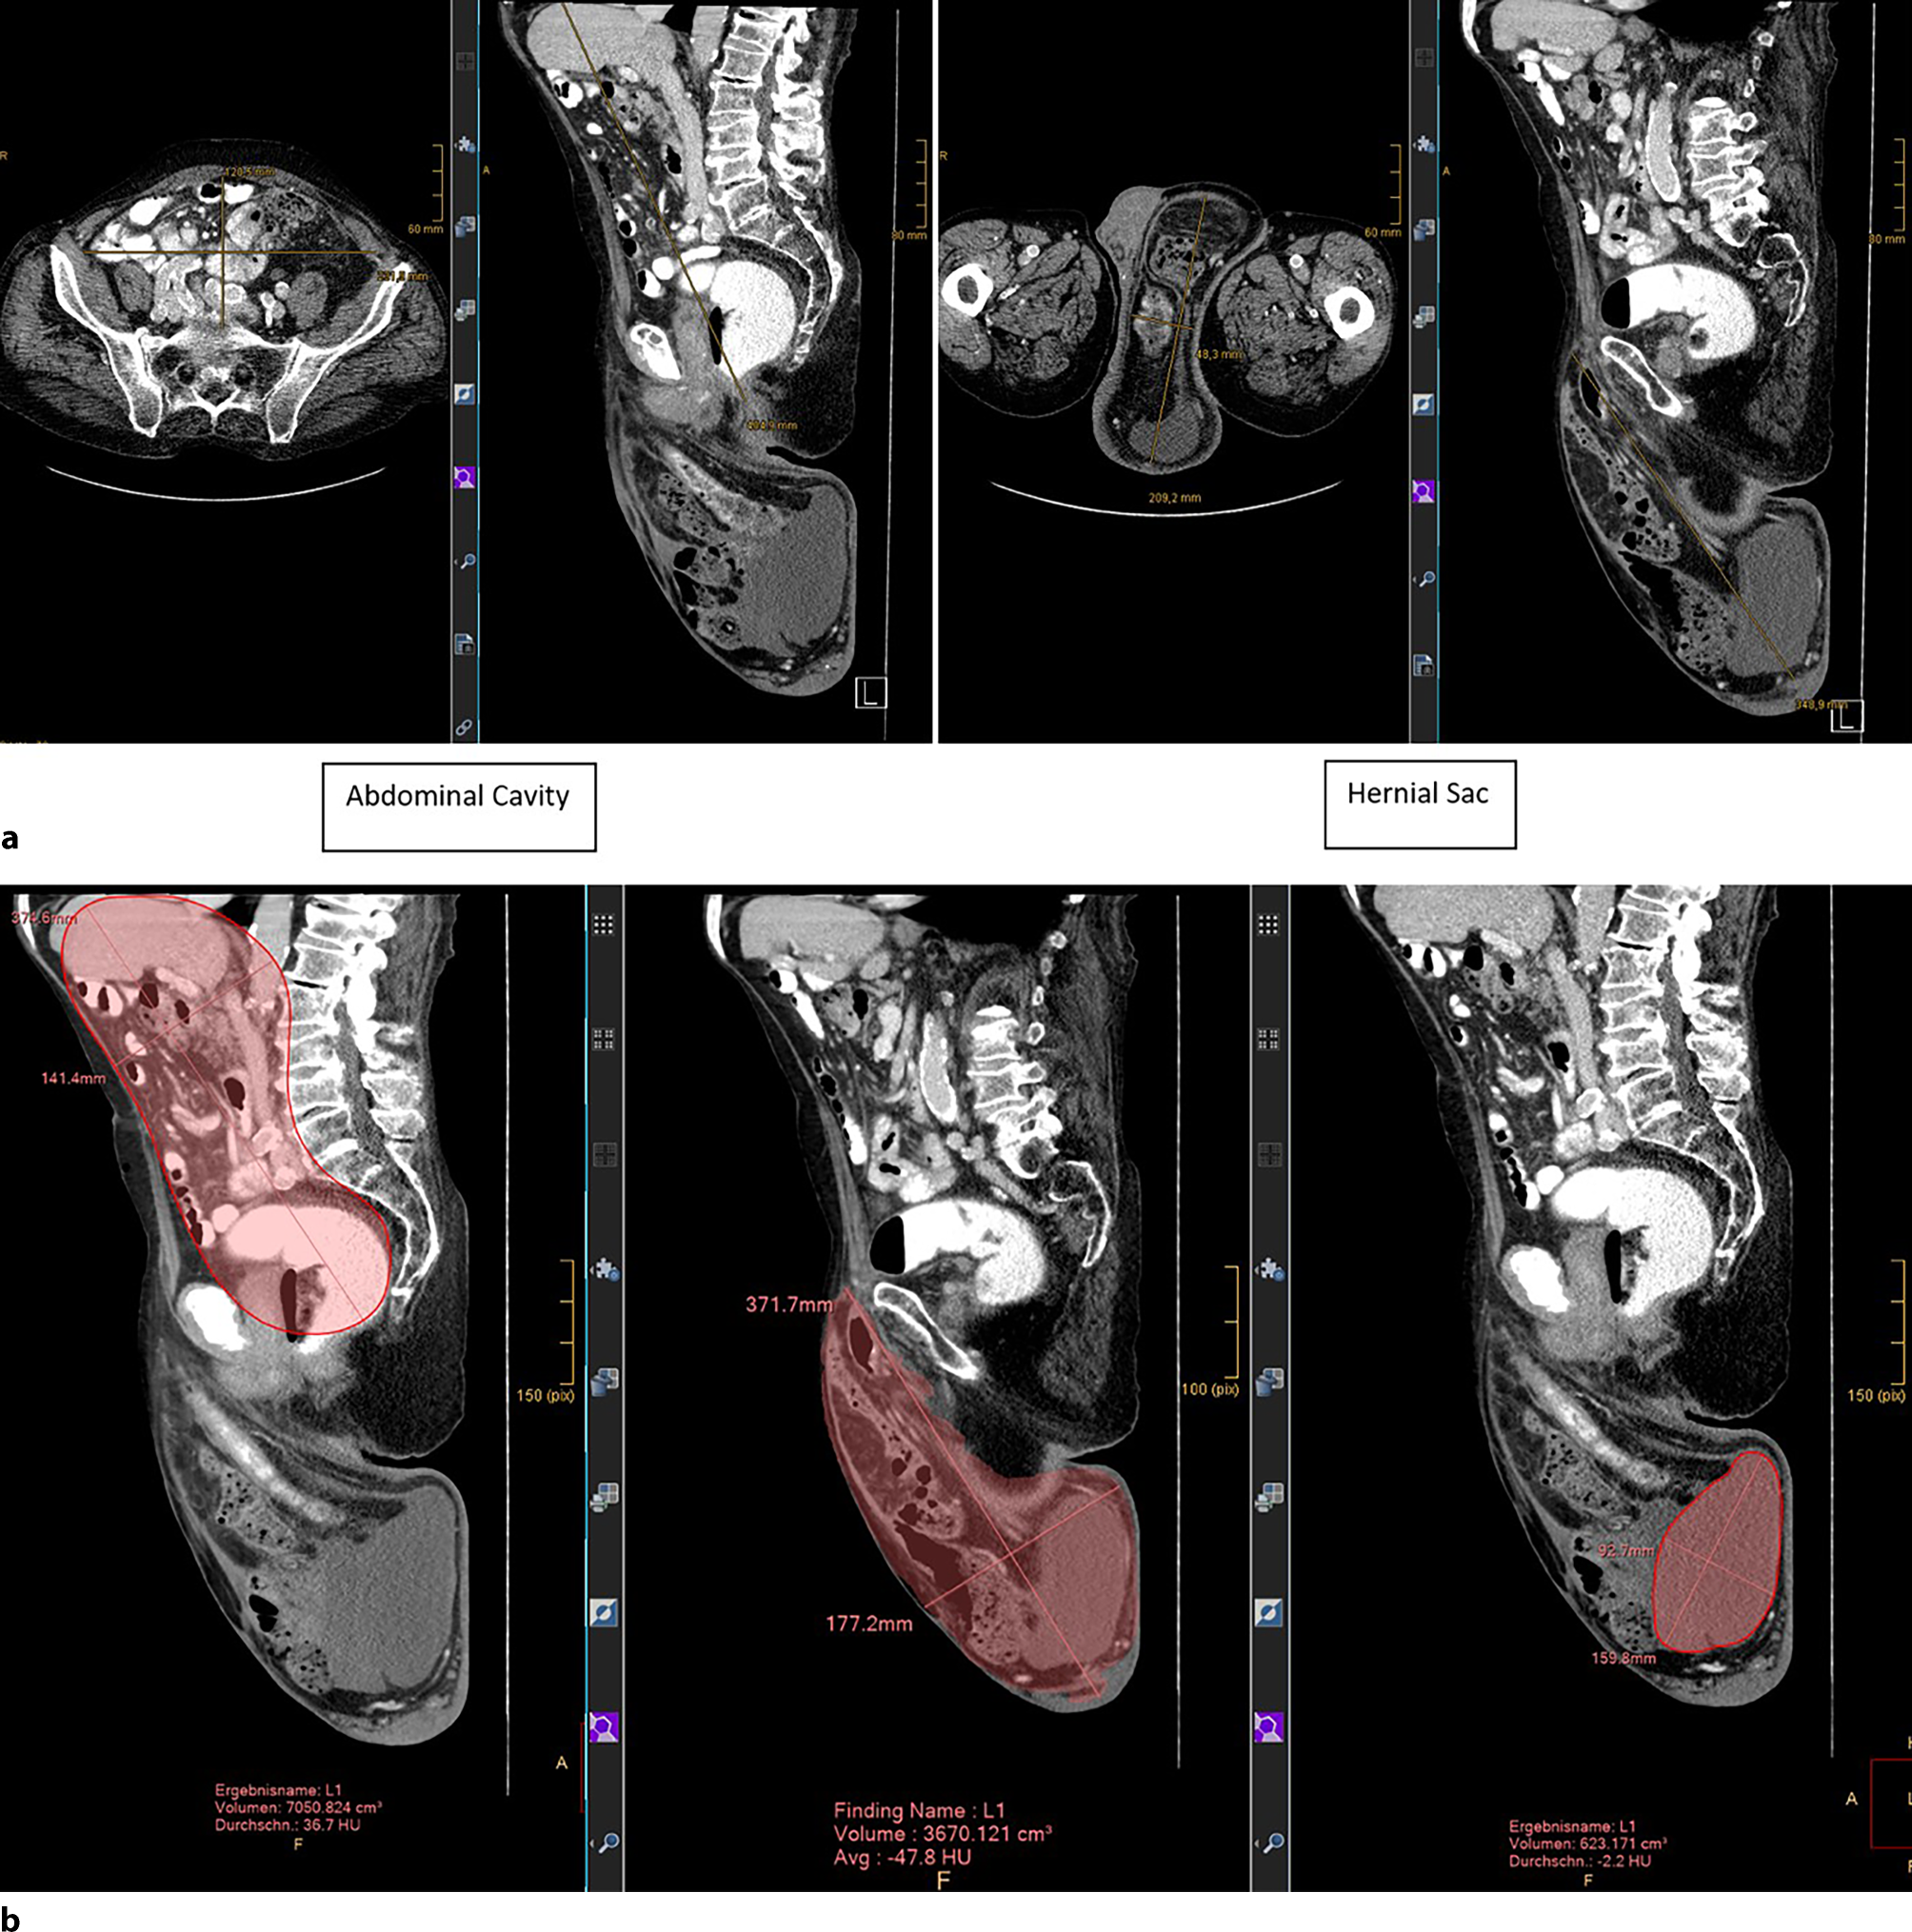

After a thorough clinical examination by two surgeons with a specific interest in hernia surgery in a tertiary care facility’s dedicated hernia clinic, anesthesiologic examination, and clarification of the patient’s extensive preoperative risk profile, a CT scan of the abdomen, pelvis, and scrotum at rest and under the Valsalva maneuver was performed. The volume of the abdominal cavity and the hernia sac were calculated in accordance with Tanaka’s method and after axis correction, a score of 0.43 radiologically supported the already clinically clearly apparent loss of domain ([7]; Fig. 3a, b). Radiological axis correction for analyses was necessary because the original methodology of calculation according to Tanaka is only applicable to ventral hernias and since the radiological configuration of inguinal hernias is not of elliptic configuration like most vental hernias but instead rather pear shaped.

Fig. 3

ab: Calculations of the extent of loss of domain

Patient information

The 73-year-old male patient was 173 cm tall and weighed 83 kg (BMI: 27.7 kg/m2). On initial presentation, he was suffering from a right-sided hernia (pL3) and a left-sided, partially reducible hernia with loss of domain (pL3) without previous abdominal surgery (Fig. 1). Coexisting medical conditions included peripheral vascular disease of the legs, grade II mitral valve failure, grade II tricuspid valve failure, atrial fibrillation, arterial hypertension, and ongoing nicotine abuse. The latter was terminated 4 weeks before the first hernia repair. This was conducted by means of a Lichtenstein operation. Botulinum toxin A (BOTOX® 100 Allergan international units, Allergan Pharmaceuticals, Westport, Ireland) was then administered to the three muscles of the abdominal wall in five positions on either side under ultrasound guidance and after dilution in 30 ml of normal saline. A CT scan was performed, which showed a loss of domain of 43% (volumes: hernia sac: 3670 ml, hydrocele 623 ml, abdominal cavity 7051 ml). Five weeks later, surgery was performed on the giant scrotal hernia on the left side. Lichtenstein’s technique of repair was chosen for the patient over potentially applicable laparoscopic procedures in view of the very large hernia and the patient’s general frailty. After a minimal additional lateral incision of the deep inguinal ring, in order to facilitate reduction of the hernia sac’s content, followed by nonabsorbable suture reconstruction of the deep inguinal ring, the implant size was chosen with regard to the patients limited anatomical space. The spermatic cord and testicle remained intact and could be preserved.